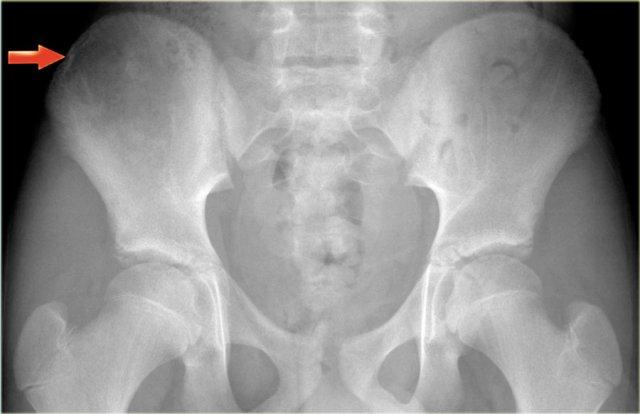

Bên trái là tổn thương tiêu xương không rõ ranh giới ở xương chậu phải của một bệnh nhân trẻ, có thể dễ dàng bị bỏ sót.

Chẩn đoán cuối cùng: Sarcoma Ewing.